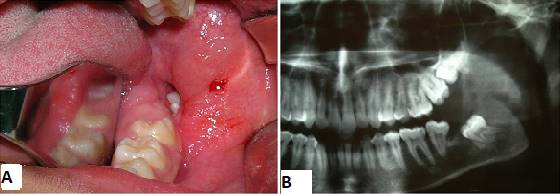

Paciente afrodescendiente, de sexo masculino, 17 años, estudiante, nacido en Fortaleza, estado de Ceará, en Brasil, que buscó atención en una clínica odontológica privada con quejas de supuración en la boca. Como nos informó la madre, durante aproximadamente un mes el paciente había sentido un mal sabor en la boca. Buscaron un cirujano dentista clínico que, al solicitar una radiografía panorámica de los maxilares, notó una lesión en la mandíbula y lo remitió al cuidado del cirujano bucomaxilofacial. En la anamnesis, no mencionó ninguna queja de dolor: solo mencionó mal sabor en la boca y mal aliento. En el examen físico extrabucal se observaron facies simétricas y ausencia de deformidades faciales. Cadenas ganglionares del complejo cervicofacial sin alteraciones. En el examen intrabucal era visible una supuración en la región del surco gingival lingual y distal 37. Elevación discreta en la región del trígono retromolar izquierdo con punto de fluctuación, de consistencia líquida. Examen de imagen (ortopantomografía) que muestra una extensa lesión osteolítica en la región del ángulo y rama ascendente mandibular izquierda, de aspecto expansivo, asociada al 38 incluido desplazado hacia el hueso basilar (Fig. 1).

Para una mejor evaluación de la extensión de la lesión, se solicitó una tomografía volumétrica de haz cónico de la región, donde se pudo observar sus límites y relaciones anatómicas circundantes (Fig. 2).